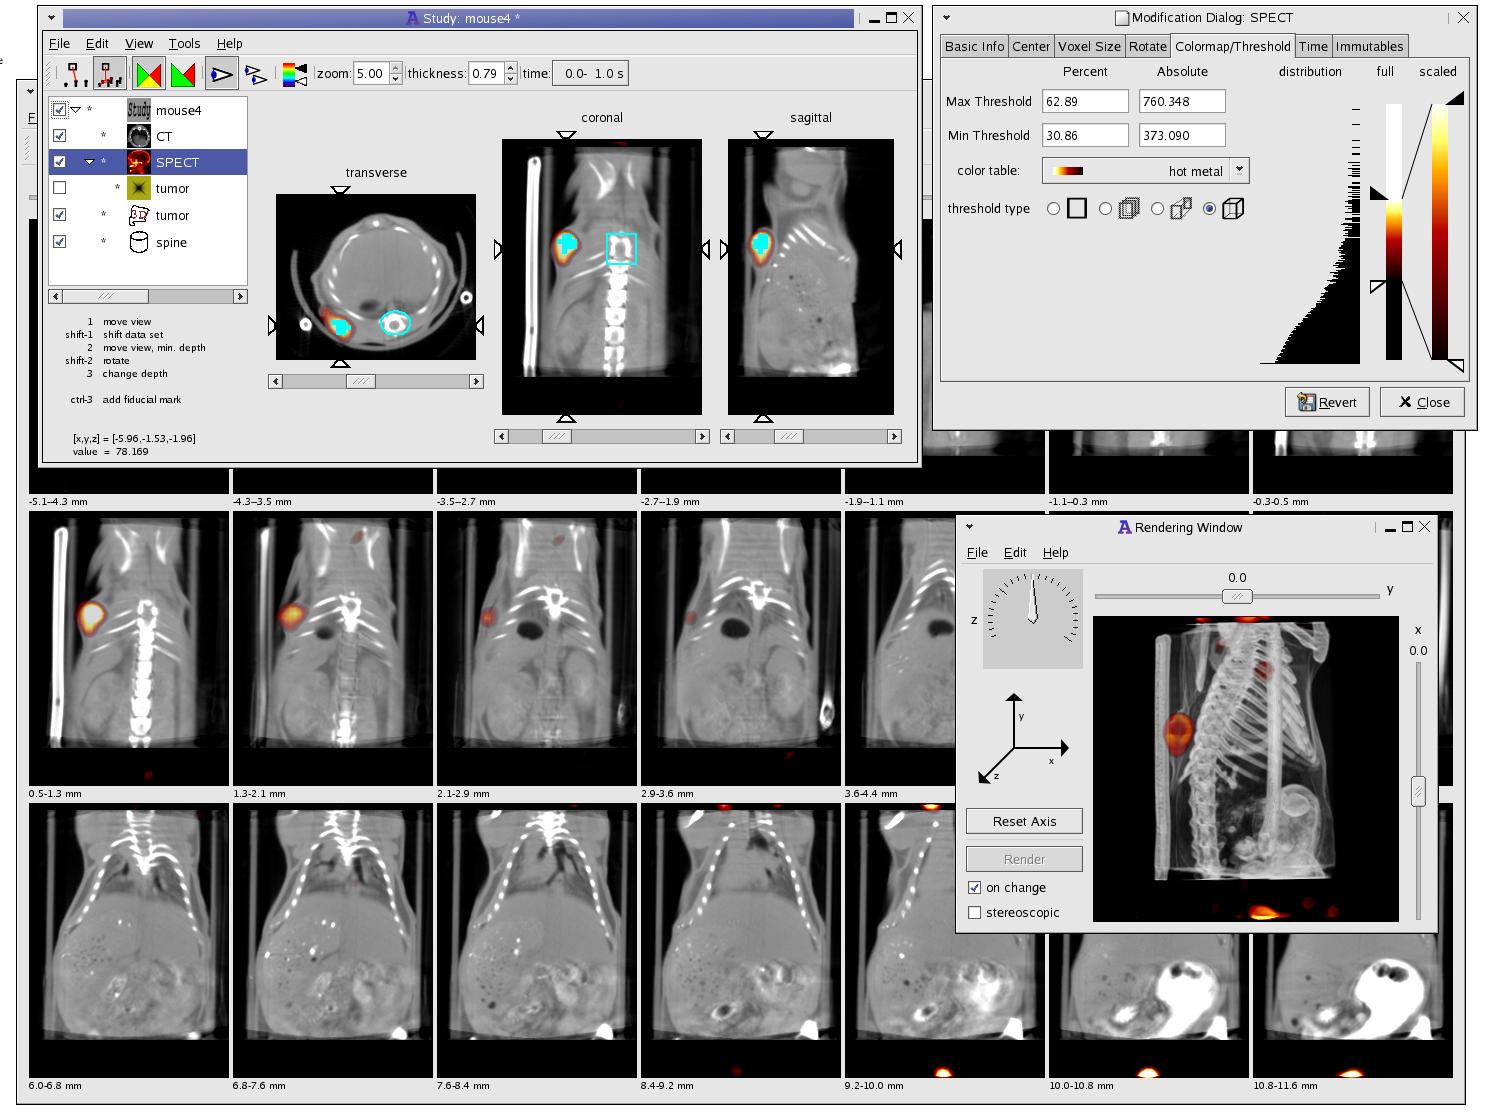

Лазерная камера для печати медицинских изображений на пленке стандарт dicom